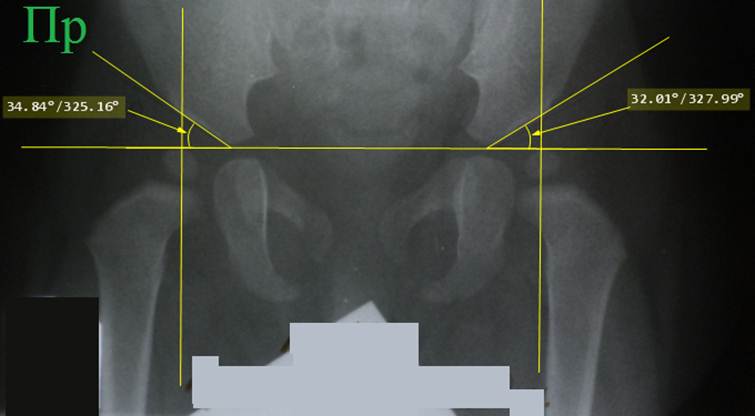

Схема

Садофьевой применяет другой метод определения положения головки бедренной

кости, который меньше зависит от возраста. Черчение начинают с проведения линии

Хильгенрейнера и линий крыш вертлужных впадин, проводят измерение ацетабулярных

углов. Затем отрезок линии крыши вертлужной впадины, который соприкасается с

тенью кости, нужно разделить на четыре равные интервала, которые нумеруются в

направлении изнутри к наружи. Через центр видимой на снимке шейки бедренной кости следует

провести осевую линию и пересечь ею размеченную зону линии крыши. Если

пересечение произошло в 1 интервале, то положение головки бедра нормальное,

если во 2 интервале, то положение головки бедра тоже нормальное. Если

пересечение произошло в 3 или 4 интервале, то имеет место подвывих головки

бедра, а если ось пересекла линию крыши кнаружи от ацетабулярной впадины, то

имеется вывих головки бедра. У схемы Садофьевой тоже есть недостаток:

проведение оси шейки происходит практически на глаз: там просто нет возможности

от чего-то взять параллель, потому что видимые части шейки короткие и

изогнутые.

Снимок

того же ребенка, что в предыдущем примере. Выполнено расчерчивание по схеме

Садофьевой. Справа ось головки пересекает линию крыши во второй четверти, что

относится к норме. Слева ось головки

пересекла линию крыши в третьей четверти, что свидетельствует о дисплазии

сустава. Рисунок отчетливо демонстрирует недостаток схемы, связанный с

трудностью правильного проведения оси шейки бедра. Схема крайне чувствительна к правильности

укладки.